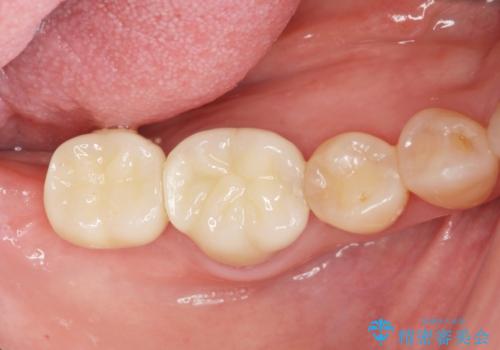

咬合機能を回復する奥歯のインプラント治療

第二大臼歯は失ってしまうと咀嚼効率が10-30%程度低下してしまうと言われている、食事で物を噛み切るのに非常に重要な歯です。

失ってしまった奥歯をインプラントを用いて咬合機能回復することで、残っている他の歯を守ることにもなります。